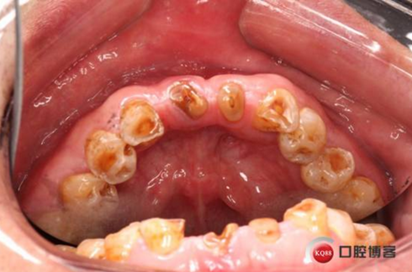

下圖是術前資料

患者,男性,47歲,全身情況良好,無手術禁忌,口內(nèi)因下前牙缺損松動不美觀來院。初診檢查時發(fā)現(xiàn)患者前牙深覆合,下頜32、42缺失。31、41松動二度,切緣磨耗嚴重,可探及髓腔,無保留價值。X-RAY檢查顯示:下頜前牙區(qū)寬度狹窄,咬合空間不足,無法行常規(guī)種植修復.